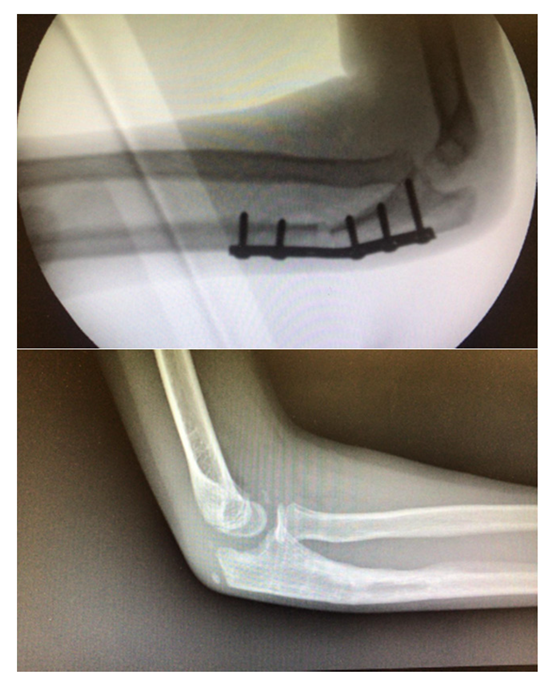

The CASS process was achieved agreeing to the surgeons’ likings and experiences; thus, patients were not consecutive and the study was not randomized. Parents and carers provided authorization for the study. The methodology described and illustrated by the example of a Monteggia lesion has been applied to all the cases reported in Table 4. This resulted in seven different assembly files on CREO, each one representing the phases of the respective surgery. Applying simulation to more than one pathology, involving different body segments, has enabled its effectiveness to be verified and the problems to be solved or improved. Some of the cases have already been operated and the surgeons of Rizzoli were very satisfied with the results obtained in the pre-operative planning phase, finding a considerable reduction in risks and timing during the operating phase.

The simulation results in a three-dimensional model presenting the anatomical group after the operation (Scheme 1). On it can be detected all the necessary measures in the pre-operative planning phase and the program also allows saving the file in many different types of formats so that it is exportable to other software and not viewable only by CAD.

The literature has documented the error that is made by carrying out this type of measurement on two-dimensional images, an extremely limiting procedure that easily provides inaccurate results. It is therefore necessary to obtain these quantities with the maximum possible accuracy, since a difference of a few degrees of correction determines appreciable variations in the performance of the intervention [32].

Being able to rely on these tools leads to an improvement in the clinical outcome, lower risks for the patient and reduced post-operative recovery times; the R.X. exam is not performed, with a consequent decrease in the patient’s exposure time to X-rays, plus, the reduction in the timing of the intervention allows a lower anesthetic dose for the patient. This method is particularly advantageous because it allows surgeons to evaluate, before surgery even, which surgical accessories are best suited to the specific anatomical geometry, as shown in the case of femur afflicted with Ollier syndrome. The dimensions of screws, plates and other surgical supports are defined in the catalog and, following the traditional practice, the surgical room must be equipped with a wide variety of tools to be able to meet any need; to be able to decide in advance the dimensions of the screws that realize the desired support allows even more reductions in the times and the risks associated with the intervention, as well as to greatly limit the dimensions in the operating room.